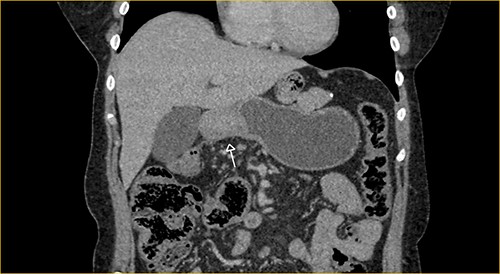

Laboratory examination showed anemia. An excluded stomach distention and parietal thickening of the pylorus and antrum were identified during abdominal computed tomography (CT) and magnetic resonance imaging (Figs 1–4). Thoracic CT was normal.

Portal phase transversal section image on CT showing excluded stomach distention with parietal thickening of the pylorus and antrum (arrow).